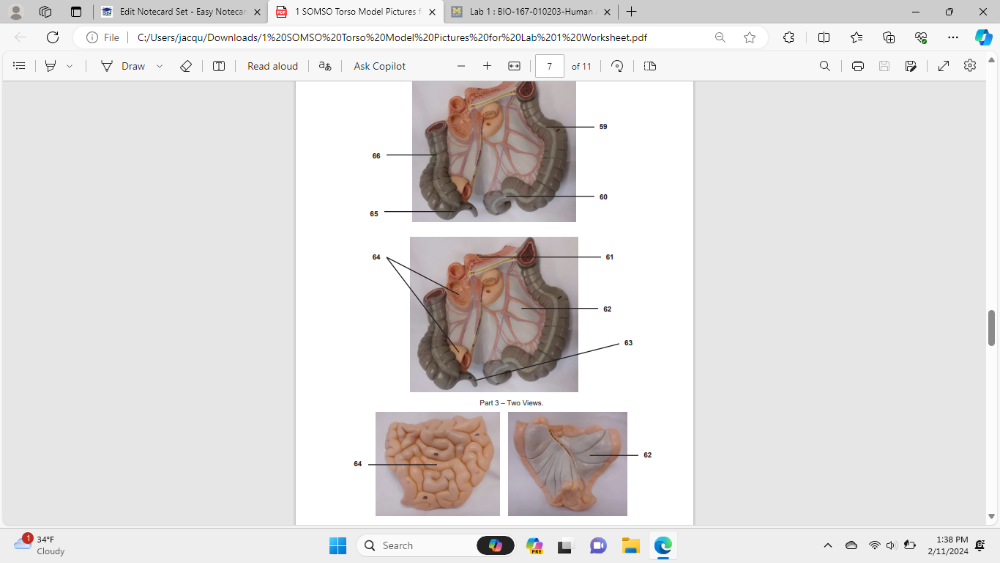

Identify the specific organ (be specific) labeled 59

descending colon

Identify the specific organ (be specific) labeled 60

sigmoid colon

Identify the specific organ labeled 61

pancreas

Identify the specific organ/structure labeled 62

mesentery

Identify the specific organ labeled 63

appendix

Identify the specific organ labeled 64

small intestine

Identify the specific organ (be specific) labeled 65

cecum

Identify the specific organ (be specific) labeled 66

ascending colon

Identify the specific organ (be specific) labeled 67

transverse colon